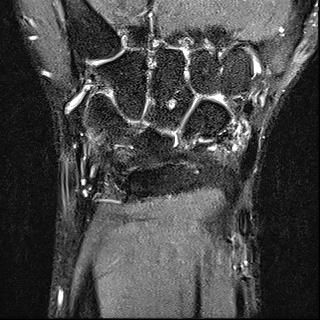

mri는 23년 부분파열 당시

2023년 MRI 영상을 보면, 삼각섬유연골복합체(Triangular Fibrocartilage Complex, TFCC)에 전반적인 신호 변화와 함께 척골 부착부 근처의 손상 소견이 확인됩니다. 당시 봉합술을 시행한 것은 임상적으로 타당한 판단이었습니다. 이후 경과가 양호하다가, 2025년 12월 요골·척골 원위부 골절이 발생한 점이 현재 상황의 핵심입니다.